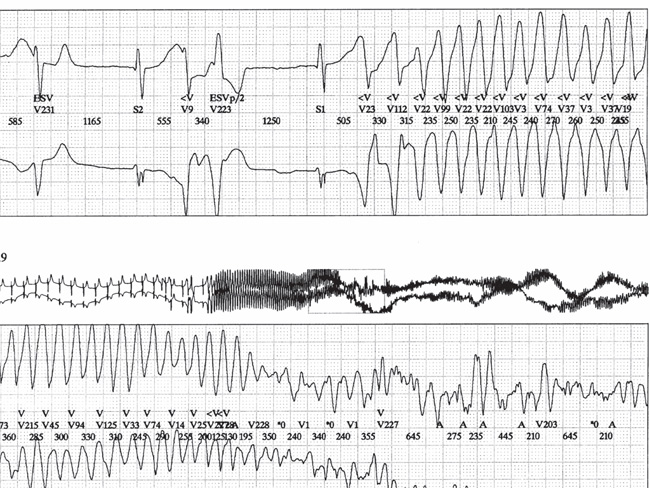

Important Dysrhythmias To Be Recognized In Er Ventricular Download Scientific Diagram